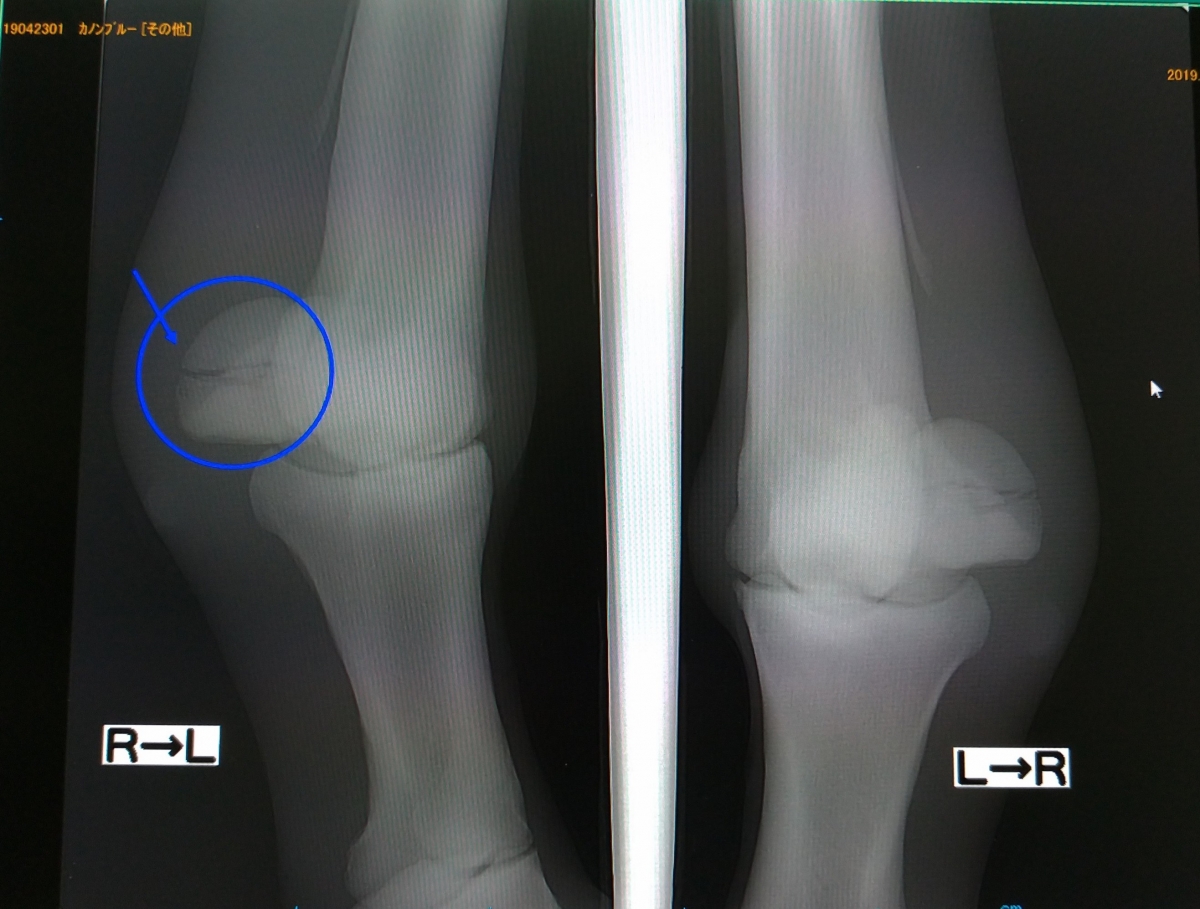

前走(5月30日)のレース後に左前の歩様が悪くなったのでレントゲン撮影をした所、左前の種子骨を骨折していました。現在は骨折の為患部には腫れと熱感があります。歩様はレース翌日からだんだん良くなってきましたが、まだいくらか気にしています。また以前から右前脚は歩様には出していませんが骨膜炎もあります。競走馬として再起は厳しいですが力はある馬なので繁殖牝馬としての活躍を願っております。(園田競馬・諏訪貴正調教師)